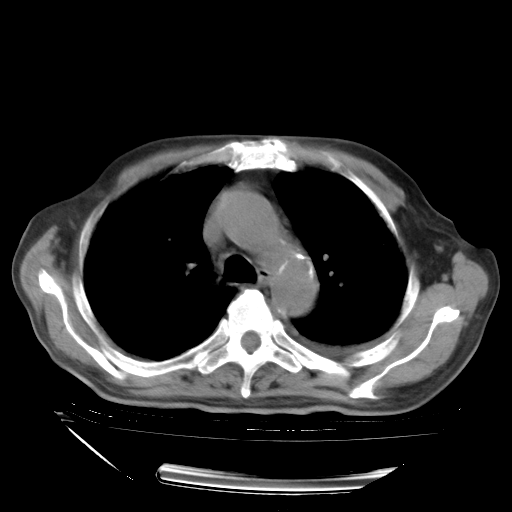

经过24天治疗,岳父的病情基本稳定。生活基本可以自理,可以下床活动。呼吸困难早已消失。体温基本正常。

只是甲强龙用80mg时血小板升到正常,改为60mg后又降到63×10*9/L。

主要治疗甲强龙80mg×14天,60mg×10天;同时抗结核(异烟肼+利福平+乙胺丁醇)。环磷酰胺0.1 tid 10天。

特别感谢胡教授、高管、桃子版主给出关键的治疗建议。桃版把所有肺部影像和全部临床资料请所在医院呼吸科、感染病科、结核科、临床免疫科专家会诊。临床免疫科专家制定了完整的治疗方案。